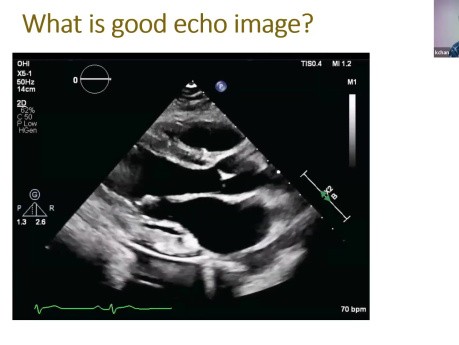

Co to jest dobre echo?

Prelegent: Kwan Chan, MD FRCPC, Professor of Medicine, University of Ottawa Heart Institute. Cele: 1) Zainicjuj dyskusję na temat tego, co składa się na dobre echo. 2) Omów kryteria jakości obrazu. 3)...